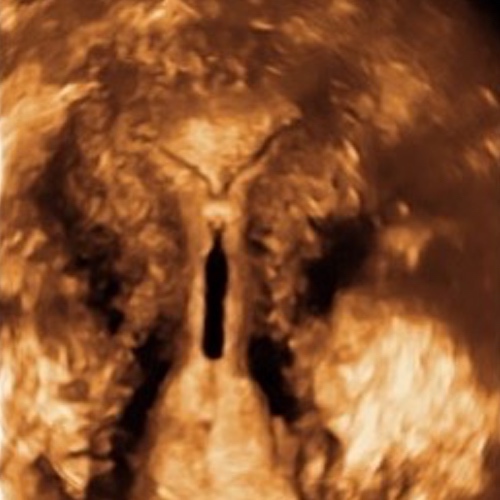

3D Bild eines perfekt sitzenden IUBTM-Kupferperlenballs.

Man sieht die relativ dünne Muskulatur am oberen Ende der Höhle (hier würde eine Kupferkette z.B. nicht verankert werden können). Auch fällt auf, dass die Höhle nur die 15mm Durchmesser "zur Verfügung" stellt. (Die kleinste herkömmliche Spirale braucht fast doppelt so viel Platz).

Gleiches Bild zum vereinfachten Verständnis. Kupferperlen liegen in der Mitte der Gebärmutterhöhle. Der Gebärmutterkanal ist aufgehellt. Die Gebärmuttermuskulatur ist in der Originalfarbe geblieben. Das umliegende Gewebe (im wesentlichen Darmschlingen) ist grau.